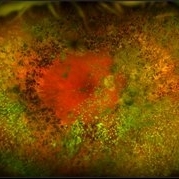

Ocular Parasitosis

Color fundus montage of an 12-year-old boy with ocular parasitosis affecting his left eye. Patient presented with decreased vision and recent travel to Florida. The specimen was lost in the lab and was never recovered.

Photographer: Olivia Rainey

Imaging device: Topcon 50dx

Condition/keywords: color fundus photograph, color photo, intraocular foreign body, left eye, montage, parasite